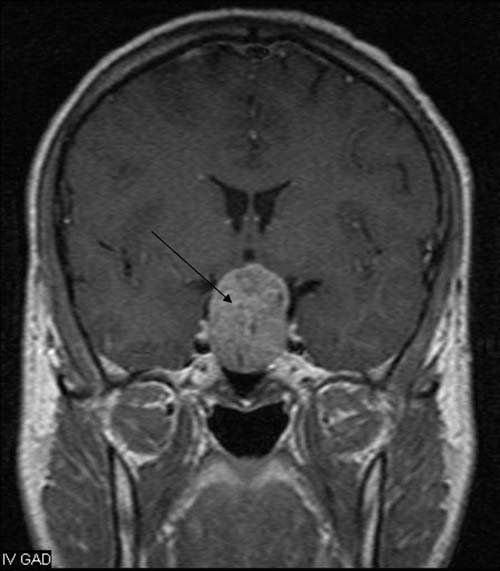

Radyolojik Görüntüler

Endoskopik Hipofiz Ameliyatları